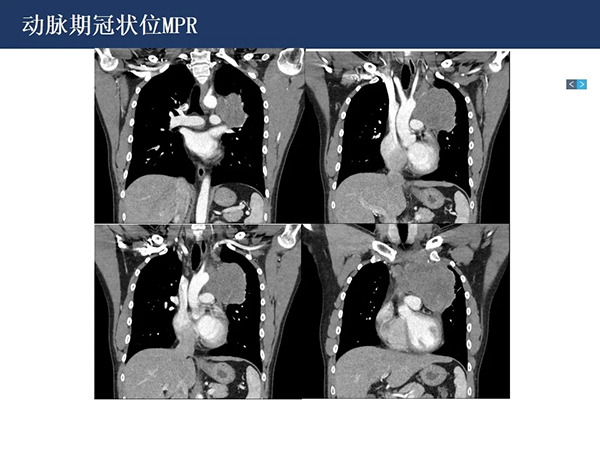

【院庆51周年】放射科:纵隔淋巴瘤